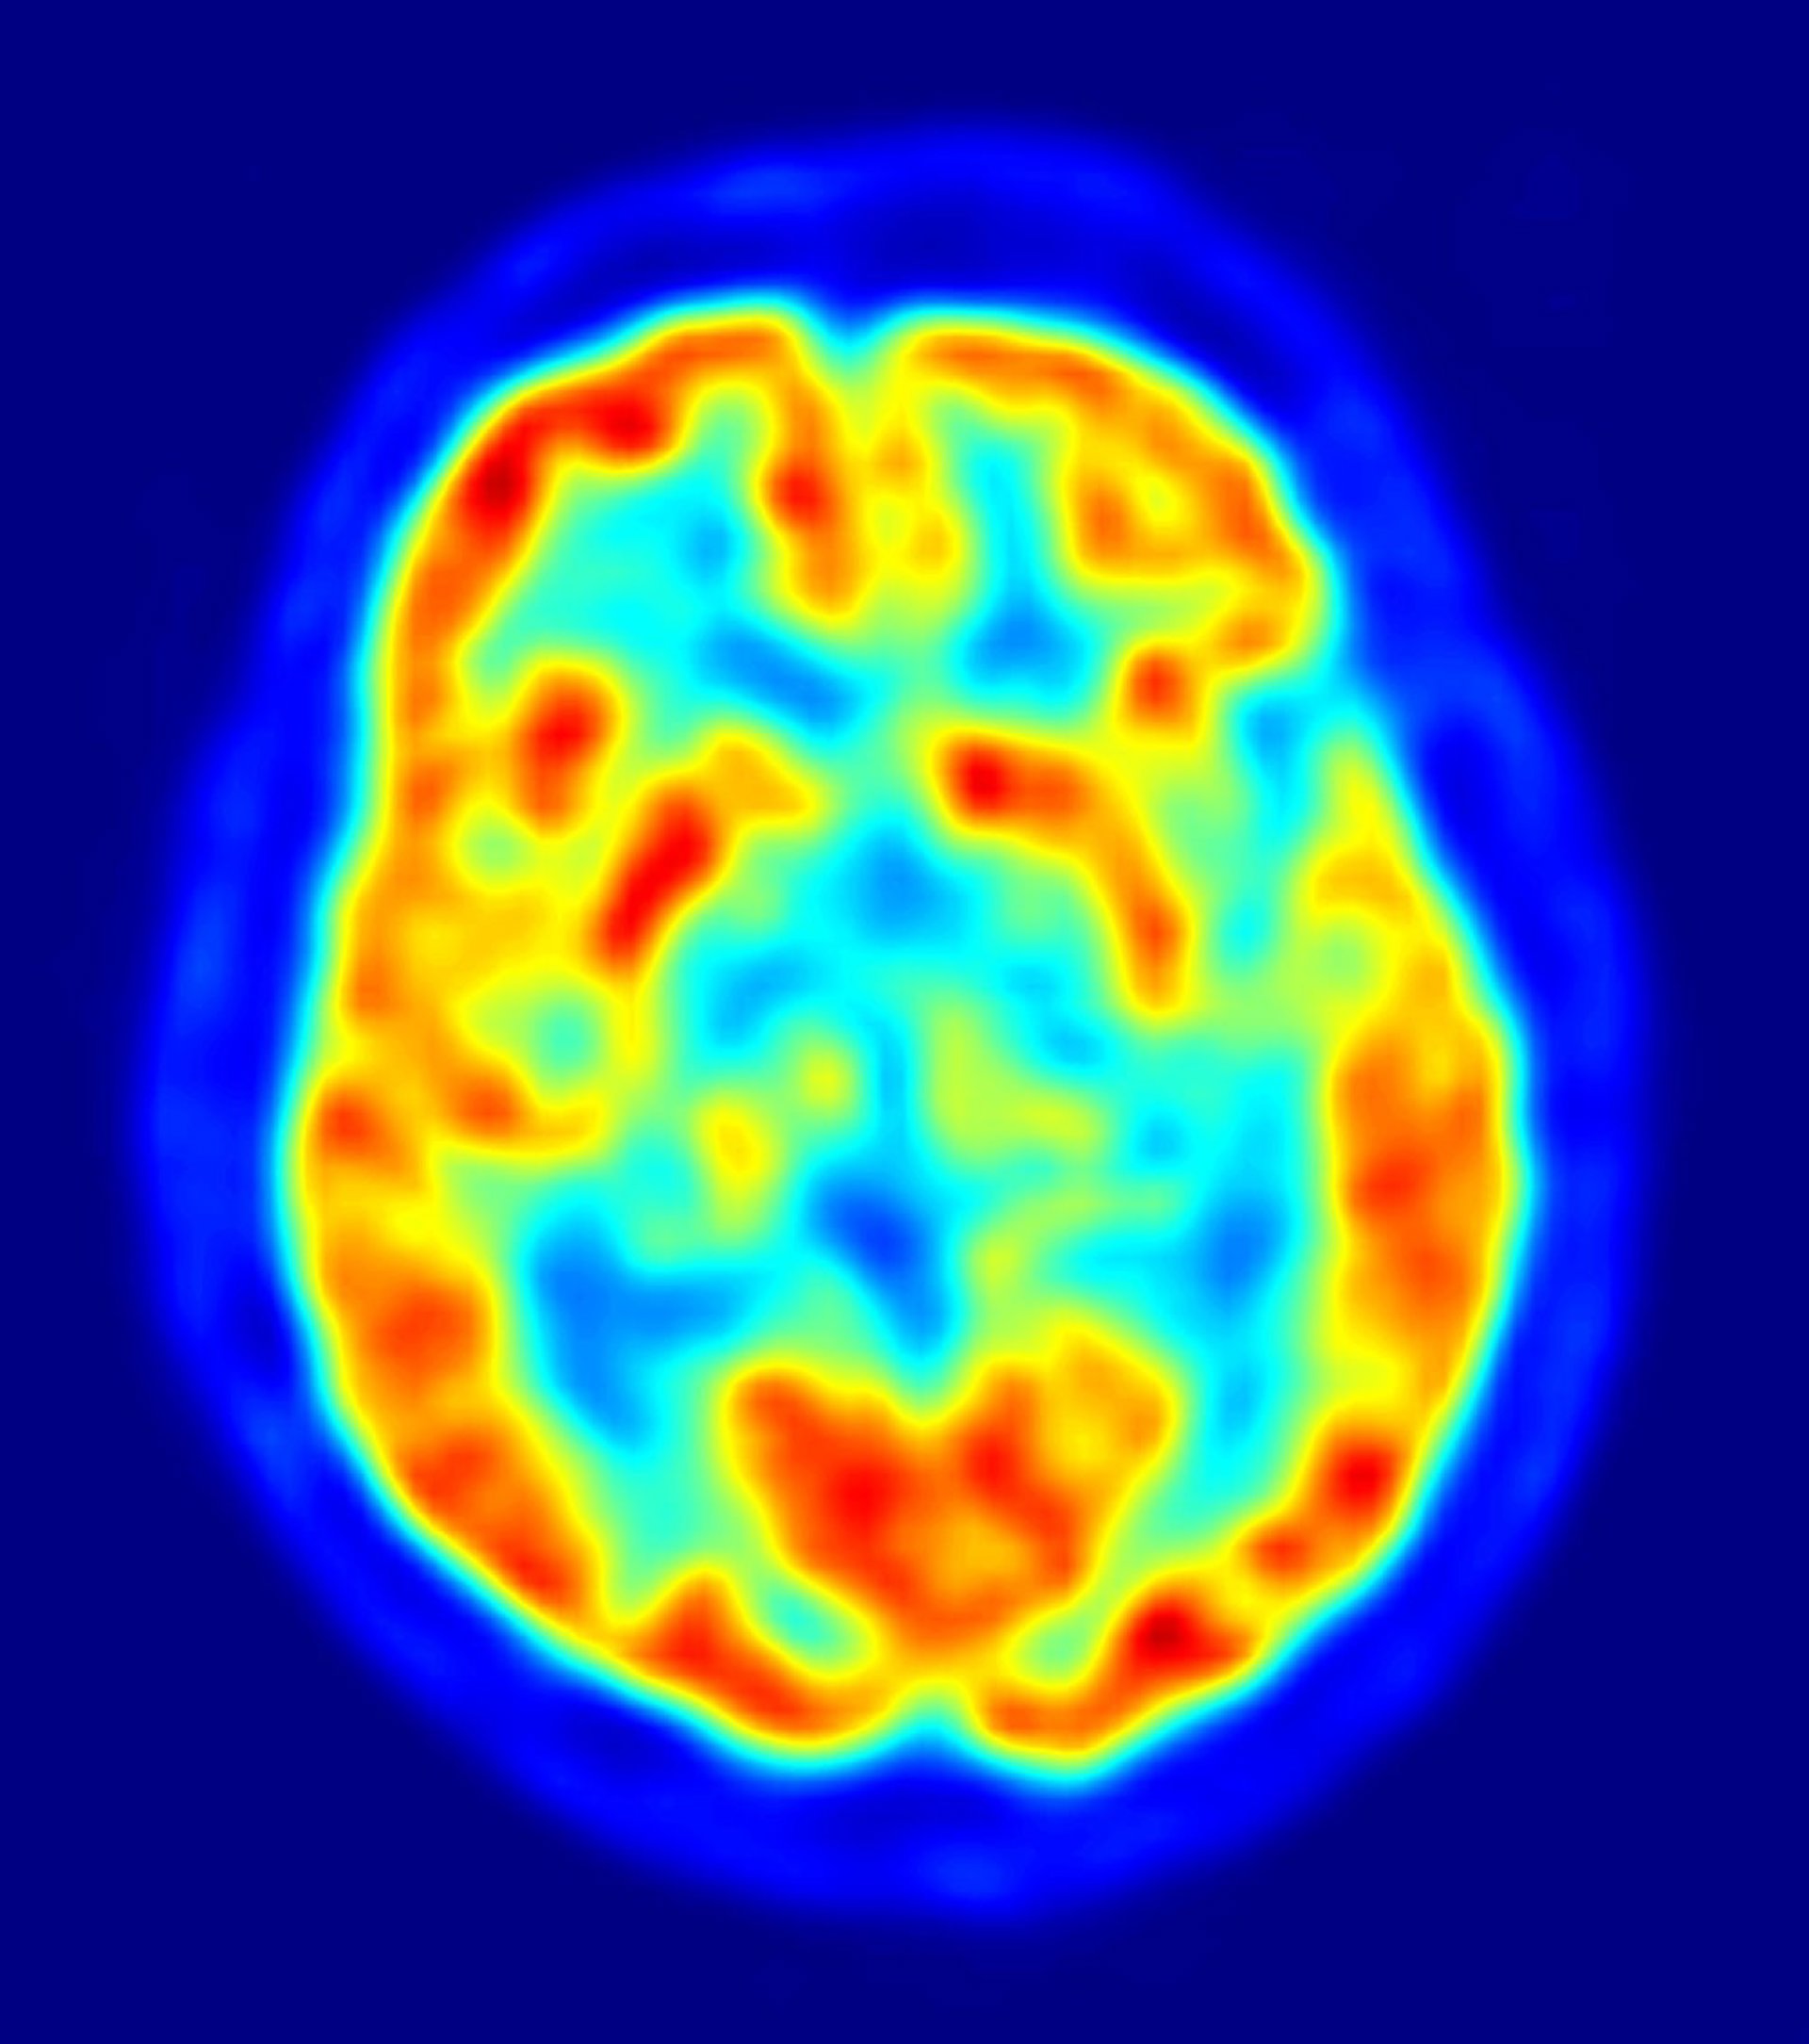

cerebro, recurso, neuronas

JENS LANGNER